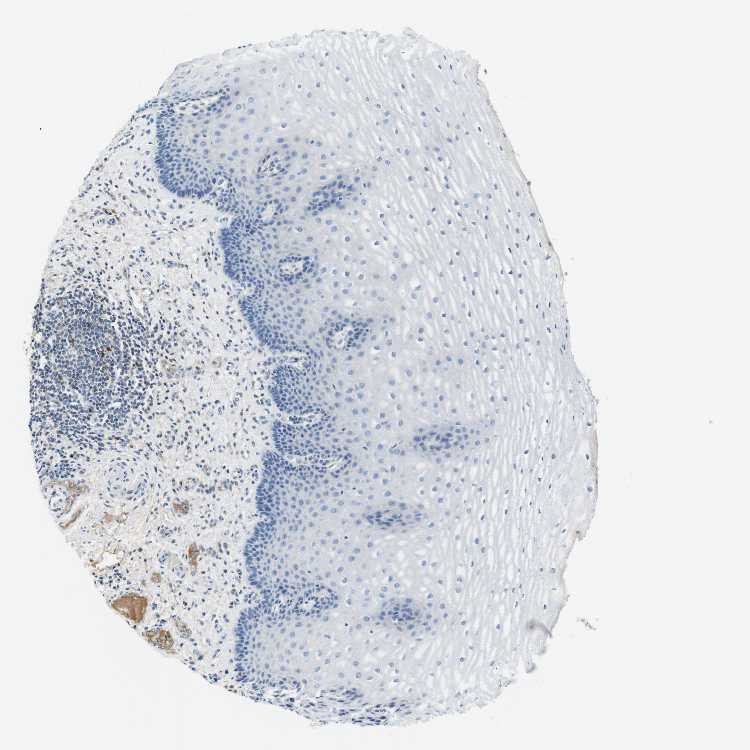

ESOPHAGUS - Antibody stainingi

Antibody staining in the annotated cell types in the current human tissue is reported as not detected, low, medium, or high, based on conventional immunohistochemistry profiling in selected tissues. This score is based on the combination of the staining intensity and fraction of stained cells.

Each image is clickable and will lead to virtual microscopy that enables deeper exploration of all samples and also displays staining intensity scores, fraction scores and subcellular localization as well as patient and tissue information for each sample.

Antibody CAB012703

Squamous epithelial cells Not detected